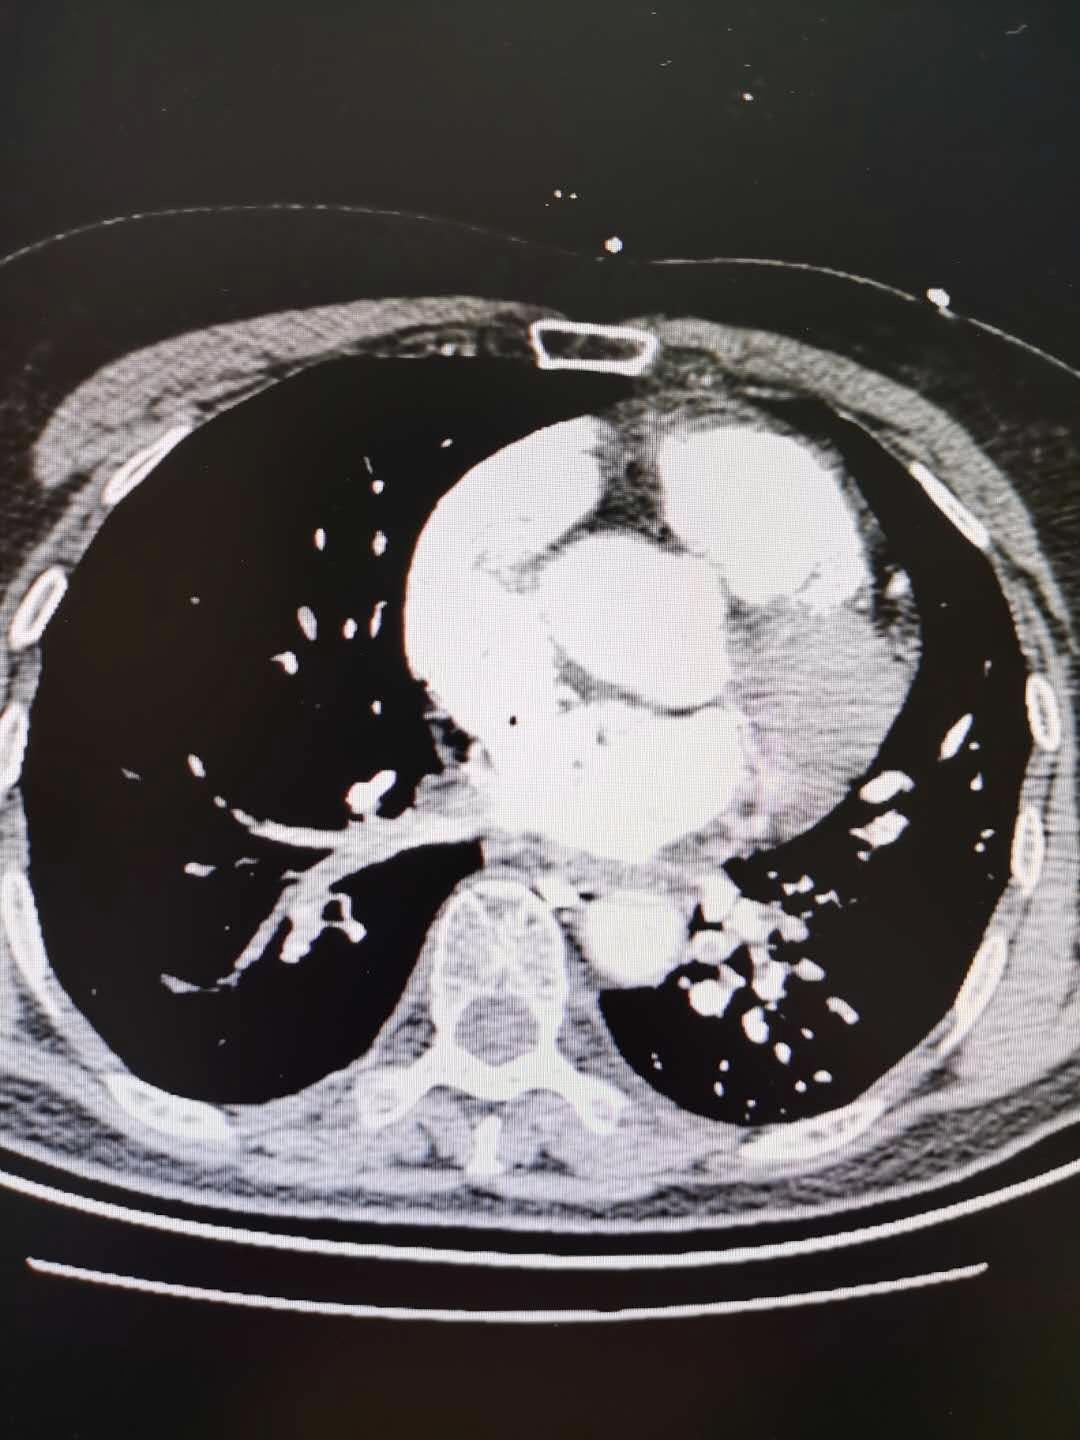

聚焦聊城市二院多学科联合救治急性肺栓塞并高出血风险的梗阻性休克